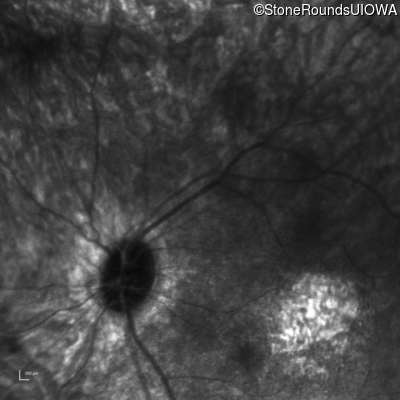

Infrared Fundus Photograph - Left - Hand Motion sc

Exemplar